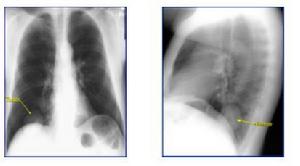

一、胸部X線檢查

本項檢查是發現腫瘤的最重要的一種方法。可通過X線透視,正、側位胸部X線攝片,發現塊影或可以腫塊陰影。進一步選用高電壓攝片、體層攝片、CT、磁共振顯像(MRI)、支氣管或血管造影等檢查,以明顯腫塊的形態、部位範圍及與心臟大血管的關係,了解肺門的縱隔淋巴結的腫大情況,支氣管阻塞、變形的程度以及肺癌有無轉移性病灶以提供診斷和治療的依據。肺癌的胸部X線檢查表現有如下幾種主要形式。

(一)中央型肺癌

多為一側肺門類圓形陰影,邊緣多多毛糙,有始有分葉表現;或為單側性不規則的肺門部腫塊,癌與專一性肺門或縱隔淋巴結融合而成的表現;也可以肺不張或阻塞性肺炎並存,形成所謂“S”型的典型肺癌的X線徵象。肺不張、阻塞性肺炎、預先性肺氣腫皆由於癌對氣管完全阻塞或部分阻塞引起的間接徵象。在體層攝片、支氣管造影可見到支氣管部分不規則增厚、狹窄、中斷或腔內腫物;視支氣管阻塞的不同程度可見有師尾狀、杯口狀況或者截平狀中斷。腫瘤發展至晚期侵犯鄰近器官和轉移淋巴結腫大,可見得有關肺門淋巴結腫大、縱隔塊狀影和氣管向健側移位;隆凸下淋巴結腫大可引起左右支氣管的壓跡、氣管分叉的高度變鈍和增寬以及食管中段局部受壓等;壓迫膈神經引起膈麻痹,可出現膈高位和矛盾運動;侵犯心包時,可引起心包積液等晚期徵象。

(二)周圍型肺癌

常呈預先性小斑片狀陰影,邊緣不清,密度較淡,易誤診為炎症或結核。如動態觀察腫塊增大呈圓形或類圓形時,密度增高,邊緣清楚常呈分葉狀,有切跡或毛刺,尤其是細毛刺或長短不等的毛刺。如癌向肺門淋巴結蔓延,可見其間的引流淋巴乾增粗呈套索狀,伊可引起肺門淋巴結腫大。如發生癌性空洞,其特點為口動壁較厚,多偏心,內壁不規則,凹凸不平,也可伴有液平面。易侵犯胸膜,引起胸腔積液,也易侵犯肋骨,引起骨質破壞。